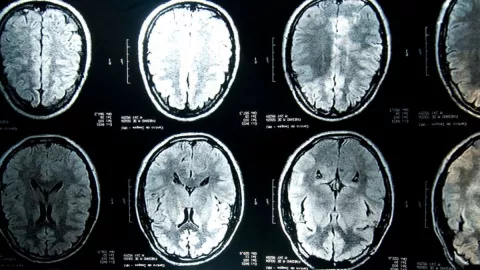

La conclusión llegó a partir de los resultados obtenidos, luego de tomar imágenes cerebrales de pacientes, antes y después del sufrir de COVID-19. En el estudio participaron 40 mil personas, de las que se tenían imágenes cerebrales, antes del inicio de la pandemia.

Con esta banco de imágenes del cerebro de miles de personas, durante el 2021, y luego del desarrollo de la COVID-19, estos pacientes fueron contactados para tomarse nuevas imágenes del cerebro y la materia gris.

“Usamos exploraciones cerebrales estructurales y funcionales de antes y después de la infección para comparar los cambios cerebrales longitudinales entre estos 394 pacientes con COVID-19″, explicaron los investigadores liderados por el profesor Gwenaëlle Douaud.

El estudio aún no ha sido sometido a estudios posteriores, ni a revisiones de pares científicos, por lo que todavía no tiene carácter definitivo. No obstante, la conclusión es determinante: los autores identificaron “efectos significativos” de la enfermedad en el cerebro con pérdida de materia gris en varias partes de este órgano.

“Nuestros hallazgos se relacionan consistentemente con la pérdida de materia gris en áreas corticales límbicas directamente relacionadas con el sistema olfativo y gustativo primario”, explica el estudio.